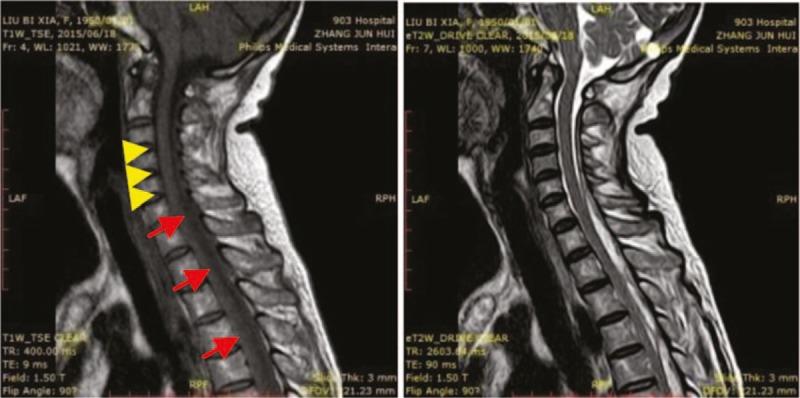

After more than 2 weeks of intensive antibiotic treatment, the epidural abscess gradually diminished in size, the white blood cell count, neutrophil count, hyperallergic C-reactive protein (CRP), and general CRP decreased, and the patient's neck and back pain resolved. After more than 4 weeks of anti-inflammation therapy, the epidural abscess was completely absorbed, and there was no relapse during the 3-month follow-up period.

经过2周多的强化抗生素治疗后,硬膜外脓肿逐渐缩小,白细胞计数、中性粒细胞计数、超敏C反应蛋白(CRP)和总CRP均下降,患者的颈部和背部疼痛缓解。经过4周多的抗炎治疗后,硬膜外脓肿完全吸收,在3个月的随访期内无复发。